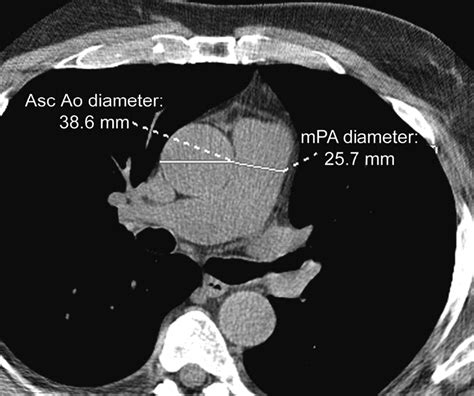

Diagnostic Guidelines for Normal Aorta Diameter

Determining the Normal Aorta Diameter is typically done using non-invasive imaging technologies like Echocardiography, Computed Tomography (CT) scans, or Magnetic Resonance Imaging (MRI). Generally, a measurement in the abdominal aorta that exceeds 3.0 cm is considered the upper limit of normal, whereas anything above 5.0 cm in the thoracic region often triggers clinical concern.

Aortic Root 2.5 – 3.7 cm

Ascending Aorta 2.5 – 3.5 cm

Descending Thoracic Aorta 2.0 – 2.5 cm

Abdominal Aorta 1.5 – 2.0 cm